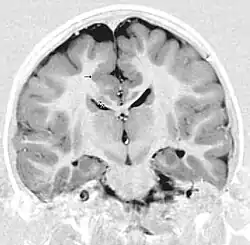

MRI głowy w projekcji czołowej u dziecka z napadami padaczkowymi; strzałki wskazują pogrubioną i nieprawidłowo zorganizowaną korę płatów czołowych obustronnie w zakrętach górnych czołowych i zakrętach obręczy. Widoczne są małe zwoje na pograniczu istoty szarej i białej. Obraz odpowiada polimikrogyrii (obecność zwojów różnicuje polimikrogyrię z pachygyrią). Ponadto, poniżej dysplastycznej kory w istocie białej ciała modzelowatego widać małe ogniska istoty szarej (podwójne strzałki), przypuszczalnie heterotopie istoty szarej